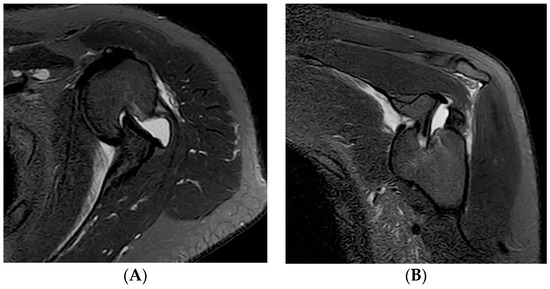

2. Case